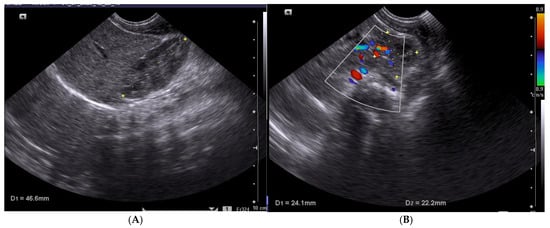

2.3. Ultrasound Methodology